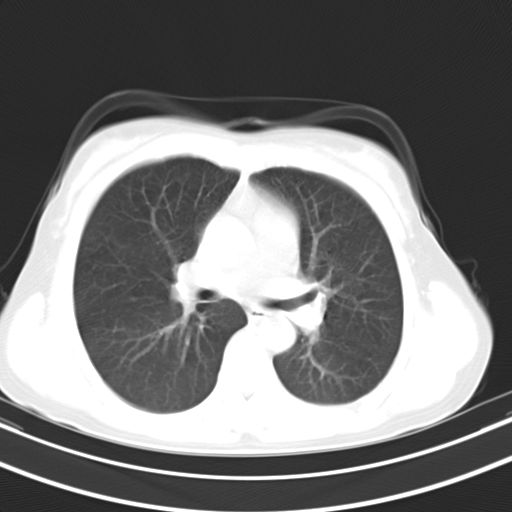

女,47岁,咳嗽胸痛一个星期,我们考虑肺结核,左下肺病灶肿瘤像不像,请高手指点。急。

右肺考虑炎症,建议抗炎后复查,左肺下叶考虑肺不张。

炎性灶;【1楔状实变影,有支气管气象,2近端纹理影增重】

右肺上叶前段积左肺舌叶炎症,建议严格抗炎后2周复查!

右肺上叶尖后段班片影不能出外肺结核。左肺舌叶三角形实变影,增强明显。考虑炎性病变

考虑两肺炎症,左胸腔积液,建议治疗后复查!

考虑炎性病变,左肺舌叶病灶需要与早期肺脓肿鉴别(结合实验室),左侧少量胸腔积液。

右肺为炎性改变,左肺病灶影像所见1、楔状实变影,边缘呈刀切样,见支气管气象,2、近端纹理影增重。

并从一元化来解释,还是符合炎性病灶。建议抗炎后复查。

两肺病变考虑炎症可能性大。(左肺病变呈楔状实变影,有支气管气象,近端纹理影增重)。

1)右肺上叶前段及左肺上叶舌段感染性病变;建议抗炎治疗后复查。2)左侧少量胸腔积液。

考虑右肺上叶前段及左肺舌叶炎症,建议抗炎治疗后复查除外结核。

左肺舌叶病灶呈扇形分布,其内可见支气管影,胸膜面光滑,不支持肿瘤病变。